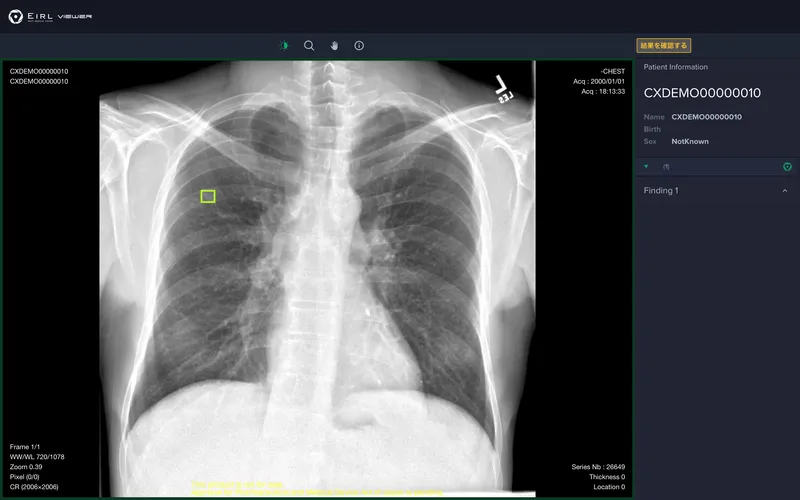

EIRL Chest Nodule

胸部X線画像から肺結節候補域を検出

・胸部X線画像から条件を満たす肺結節の形状に類似した領域(5mm〜30mmまで)[1]を検出し、医師による読影をサポートします。 ・過去に撮影された同一被験者の画像と比較し、肺結節候補域 の経時的変化(増減)を表示します。 [1]浸潤性でないもの、胸部内で他臓器との重なりがない候補域に限る。